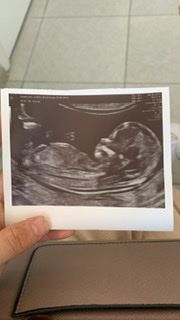

пол ребёнка

Девочка у вас. Нам на 1м скриннинге сказали пол, на втором подтвердили 🥰

Марина,это снимок узи с первого скрининга, второй скрининг жду чтобы узнать пол ребёнка

Девочка